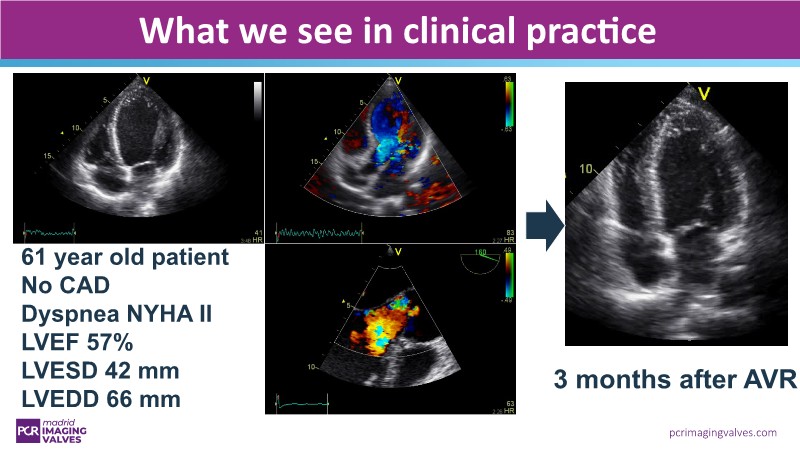

- To observe a TAVI for aortic regurgitation case with the Trilogy device from the imager’s perspective

- To understand the imaging obstacles in assessing and treating patients with aortic regurgitation